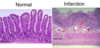

Ischemic Bowel

50% fatal– bad prognosis